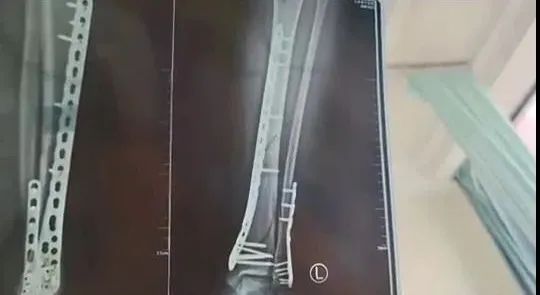

她穿7cm厚洞洞鞋下楼不慎崴脚摔倒

致使自己左腿粉碎性骨折

自己目前已做完手术在家休养

不过下地得拄拐才行

且下地有时间限制,不能久站

骨折完全康复可能需要3个月